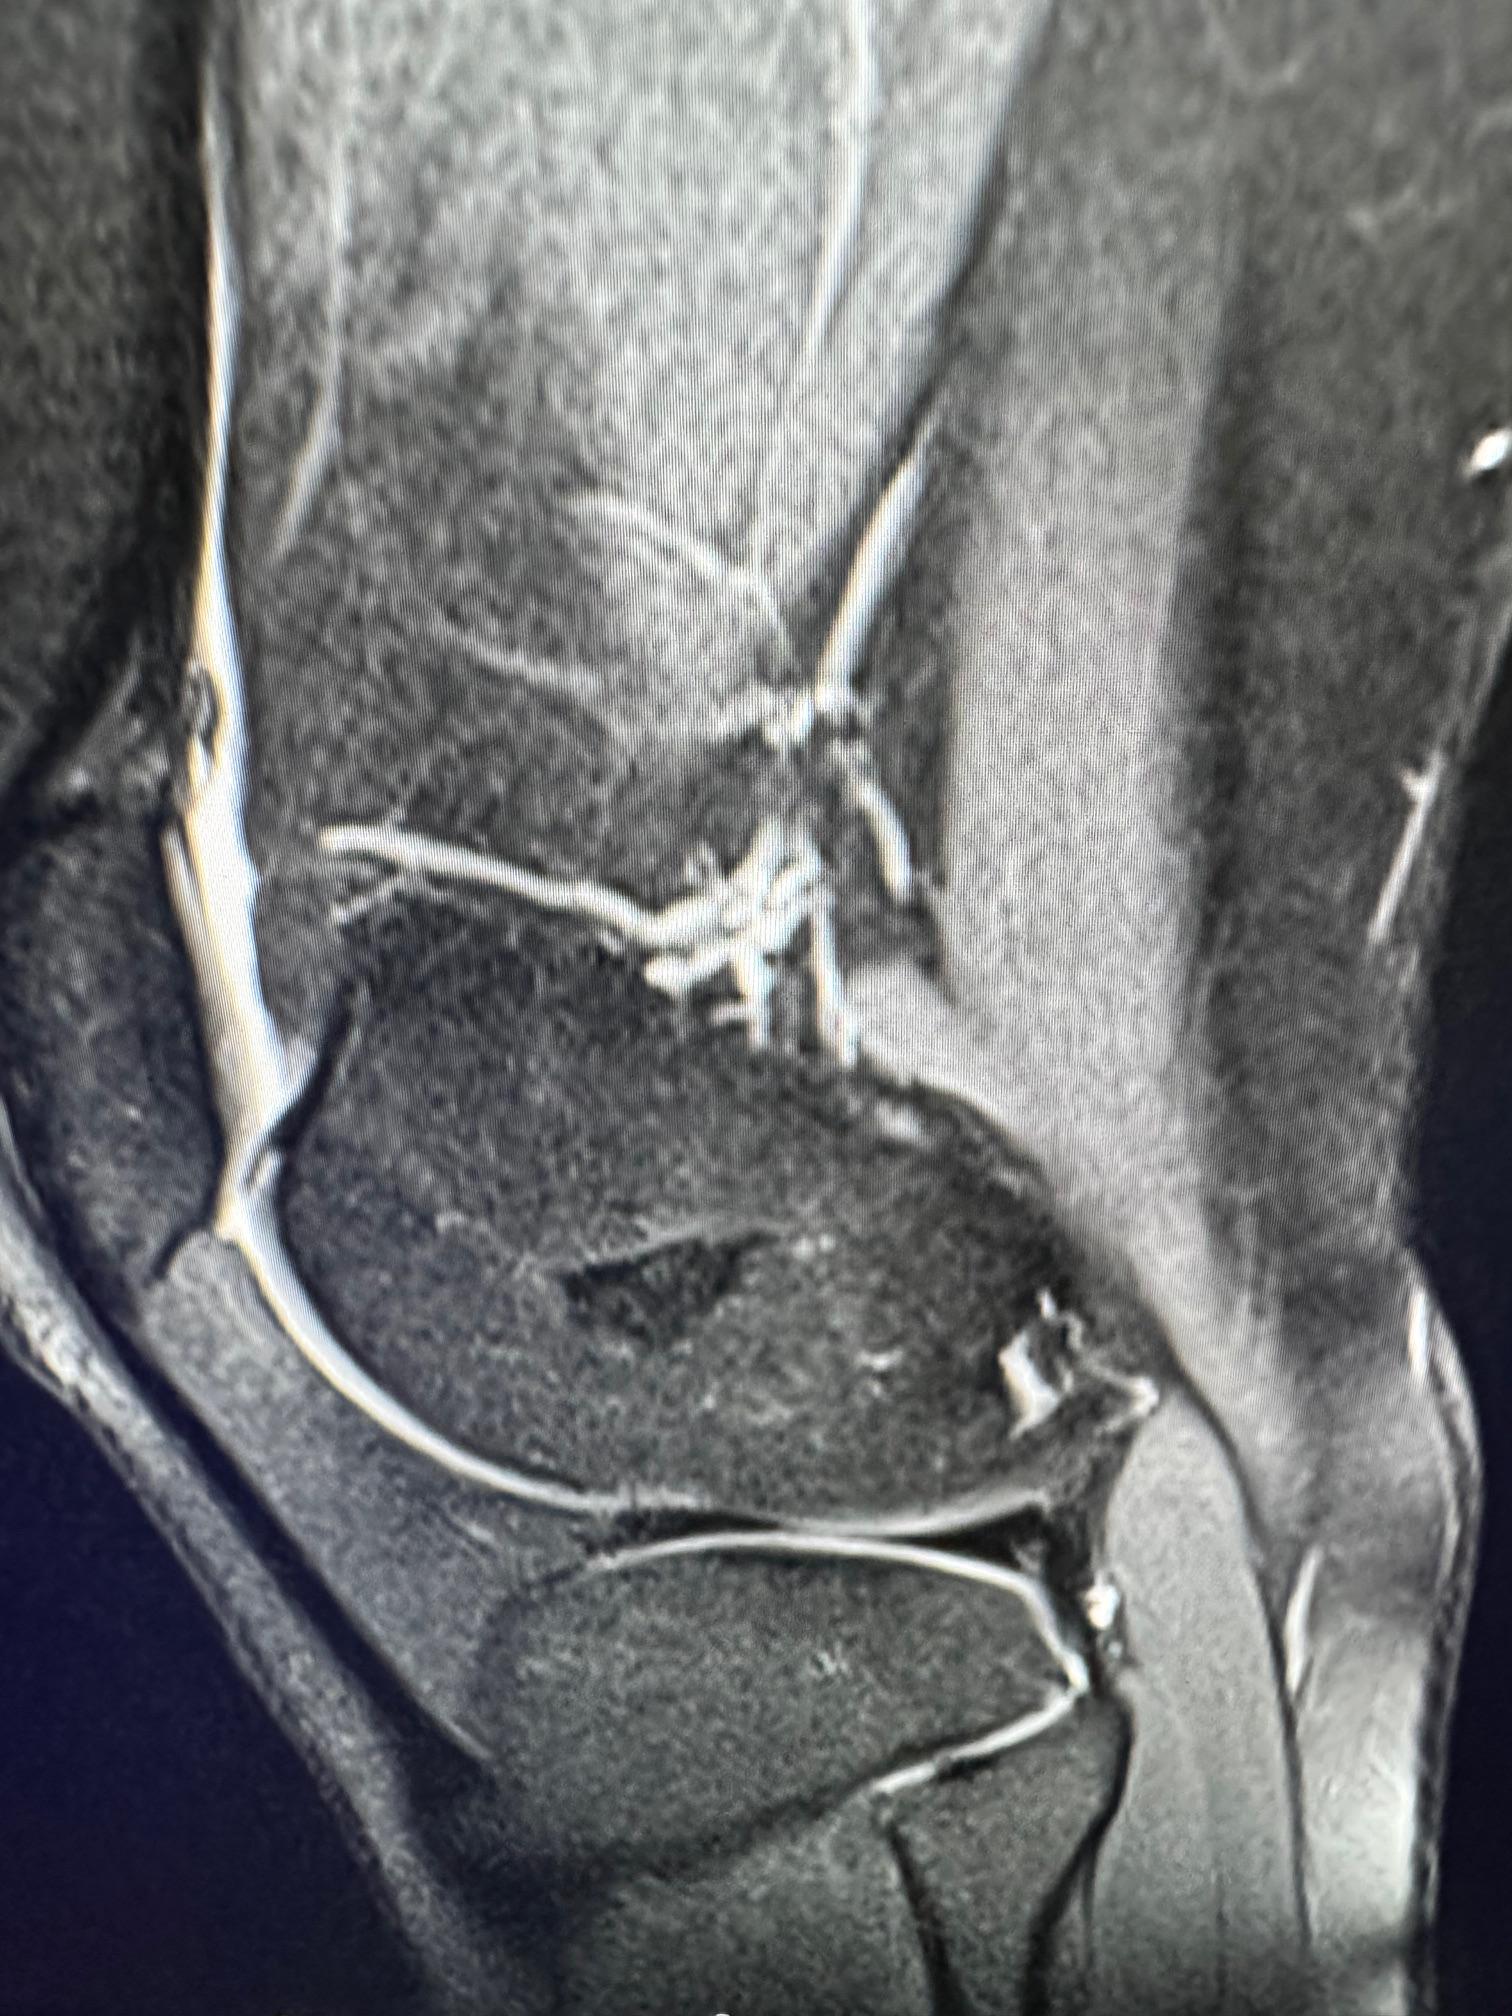

image4